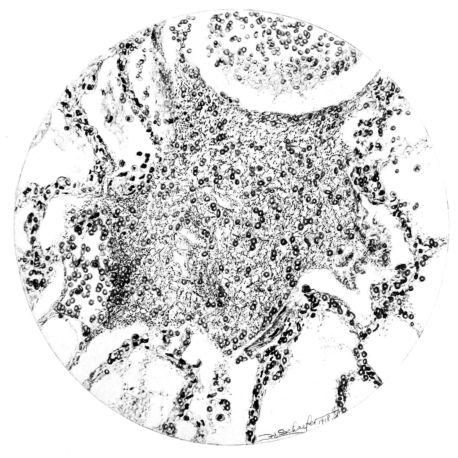

FIG. III. AUTOPSY NO. 90. DRAWING FROM A LESION OF THE TRACHEA (SOMEWHAT OLDER THAN THAT ILLUSTRATED IN FIGURE II). THE MUCOSA IS ENTIRELY LACKING. CONGESTION AND EDEMA ARE THE STRIKING FEATURES IN THE SUBMUCOSA. THE NECROTIZING PROCESS HAS EXTENDED INTO THE MUCUS GLANDS. THIS IS SHOWN IN THE LOWER PICTURE.

The changes are less marked, perhaps, in the trachea than in its finer ramifications. The mucosa is constantly more or less destroyed and large areas, usually focal, are entirely devoid of their epithelial covering. This is replaced by a sparse exudate, composed largely of red blood cells, mucus, a small amount of fibrin, and nuclear fragments (Fig. II). It may dip into the submucosa for a short distance, but usually these indentures are associated with the ducts of the mucous glands into which the inflammatory reaction extends. A more striking feature than the exudate, however, is the edema and the congestion of the submucosa. The loose areolar tissue of the submucosa is spread widely apart, and throughout it distended blood vessels are very conspicuous. Occasionally such a vessel is broken and actual hemorrhage appears in the submucosa. Occasionally, too, the inflammation extends down the duct to the mucous gland itself, and here, also, aplastic inflammatory reaction is evident, inasmuch as the acini now stain intensely red with the cells undifferentiated from each other and specked here and there by broken remains of the dead nuclei (Fig. III). After the disease has continued for a short period, even at the end of five or six days, some regeneration of the epithelial lining may be seen (3) (Fig. IV). But despite this, the acute picture persists, and there goes on, side by side, an attempted repair characterized by epithelial regeneration and the same evidence of acute change. Since the lesion is essentially a superficial one, scars or contractures of any extent are not encountered in the trachea, even in examples of the disease that have ended fatally only after many weeks.[4]